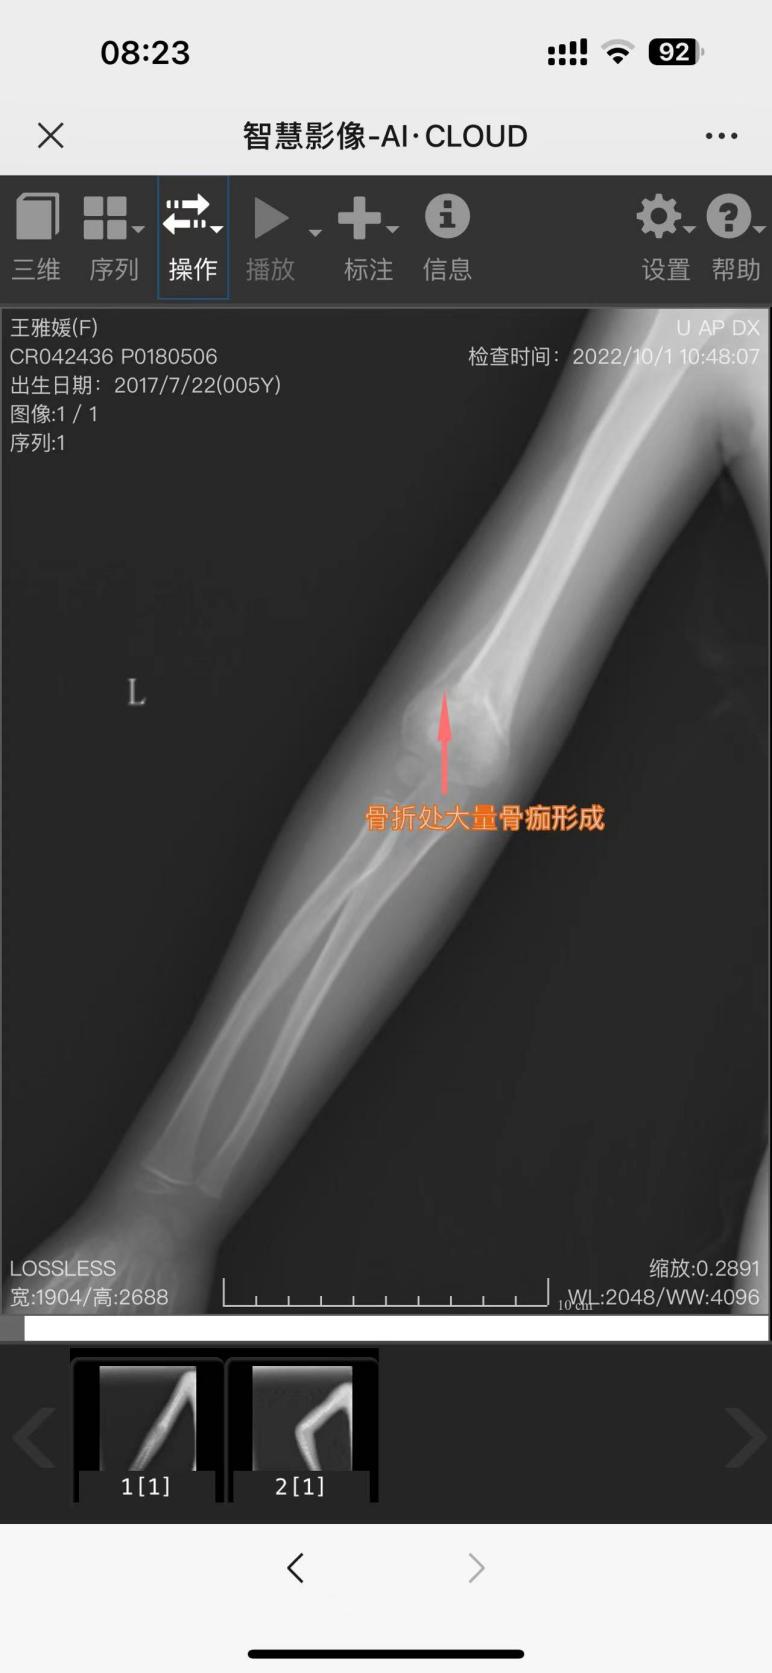

治疗后1月后复查

1年后复查